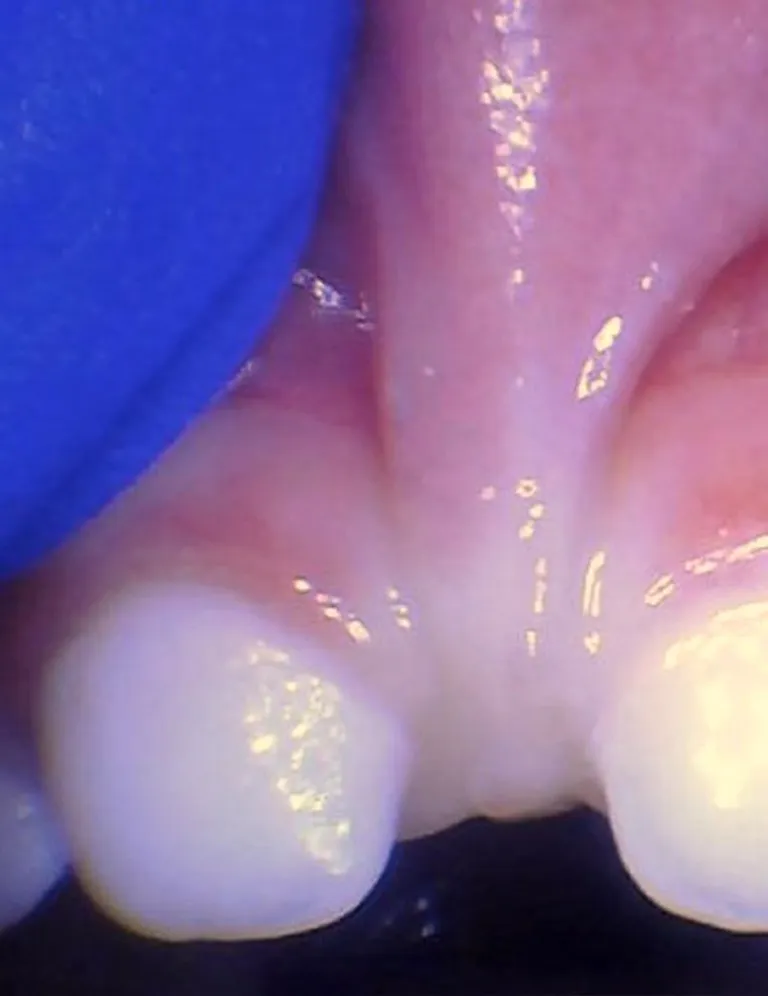

Le frein labial restrictif correspond à une anomalie où la lèvre supérieure est restreinte et ne peut pas bouger normalement. Il peut rendre difficile l'allaitement, l’alimentation, la parole et le brossage des incisives supérieures ; il peut également entraîner un diastème important (espace entre les dents) lorsqu’il est plus large que 2mm.

Il existe des spectres de restriction (site Tongue-Tie Alabama du Dr R. Baxter, Spectrum of lip/tongue restriction in infant/children), il n'existe pas une seule apparence. Il est donc important de comprendre la notion de symptomatique versus asymptomatique : un frein qui semble court ne sera opéré que s'il impacte la bonne fonction linguale, labiale ou jugale.

Photos ci-dessous issues du site Tongue-Tie Alabama avec l'accord de R. Baxter.

Enfant - Spectre de restrictions d'un FR labial